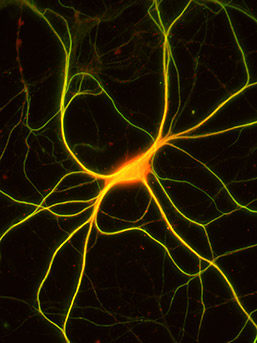

Un neurone dell'ippocampo di un topo costellato da migliaia di connessioni sinaptiche (in giallo). Immagine: Lisa BoulangerQuando si tratta di cervello, «di più è meglio» sembra un presupposto ovvio. Ma nel caso delle sinapsi, che sono le connessioni tra le cellule cerebrali, se sono troppe o troppo poche possono compromettere la funzionalità del cervello.

Questa immagine di un neurone dell'ippocampo di topo mostra i recettori dell'insulina (verde) e la proteina calbindina (rosso). In questa zona del cervello, la calbindina è presente nelle cellule granulari dentate, che formano le sinapsi sulle cellule che esprimono MHCI. L'ampia sovrapposizione (giallo) suggerisce che questo neurone, che esprime i recettori dell'insulina, è un neurone dei granuli dentati. (Immagine: Lisa Boulanger)La Boulanger era anche l'autrice senior di uno studio del 2013, pubblicato sulla rivista Learning and Memory, che aveva scoperto che i topi allevati per produrre meno proteine MHCI funzionali esibivano cambiamenti notevoli nella funzione dell'ippocampo, una parte del cervello dove si formano alcuni ricordi, e avevano gravi menomazioni alla memoria. "I livelli di MHCI sono alterati nel cervello di Alzheimer, e livelli alterati di MHCI nei topi sconvolgono la memoria, riducono il numero di sinapsi e inducono insulino-resistenza neuronale, tutte le caratteristiche principali dell'Alzheimer", ha detto la Boulanger.